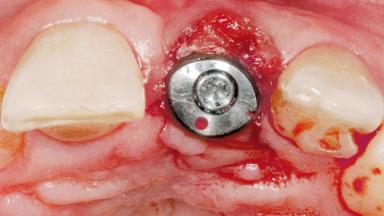

Late Flapless Placement of an Implant in a Maxillary Left Central Incisor Site

A 39-year-old male patient presented with a chief complaint of discomfort and gingival discoloration around his maxillary left central incisor. He was in good general health and was a non-smoker. His past dental history was significant because of the traumatic fracture of tooth 21 in a sporting accident at age 13. Initial dental treatment included endodontic therapy and a full-coverage restoration. The patient became symptomatic 5 years later, when structural failure of the tooth resulted in the dislodgment of the crown. Endodontic retreatment, apical surgery, and post-and-core restoration were performed.

| Soft Tissue Grafting | Simultaneous |

| Bone Volume | Deficient horizontally, requiring prior grafting |